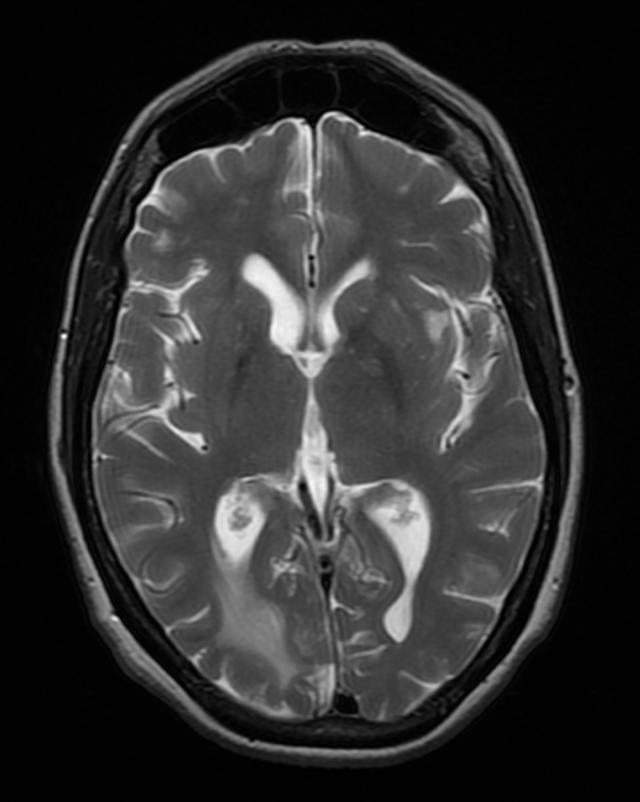

- T. gondii encephalitis presents as fever, headache, confusion, seizure, and focal motor findings with ring-enhancing lesions [Fig 4]. Patients with encephalitis may present with a non-focal, nonspecific illness, headache, and psychiatric symptoms.

- Imaging for TE is contrast-enhanced CT or MRI that shows multiple ring-enhancing lesions with surrounding edema in the gray matter of the cortex or basal ganglia.

- Occasionally, TE can present as a single lesion.

- Multifocal lesions on contrast-enhanced brain CT or MRI, especially in the basal ganglia.

- Typical radiographic appearance + therapeutic response = presumed diagnosis.

Brain toxoplasmosis

Right occipital lobe toxoplasmosis in a patient with AIDS

Source: Wikimedia commons, Jmarchn

https://upload.wikimedia.org/wikipedia/commons/f/f3/BrainToxoplasmosis_MRI_4_11.png